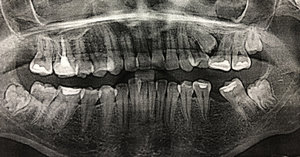

Разошлось мнение двух врачей: одна считает, что кариес на шестнадцатом есть, вторая, что его нет. На рентгене, на шестнадцатом виден темный участок, то есть, скорее кариес есть, чем его нет.

С вашей точки зрения он скорее есть, чем его нет? (речь идет не о поверхностном кариесе, который на рентгене нельзя увидеть, а о более глубоком: среднем или глубоком). Снимок был сделан до лечения.

Второй вопрос: Мне вылечили от кариеса семнадцатый и двадцать шестой зубы. Лечение производилось от двух до трех недель назад. До этого жевать было удобно, как твердую, так и мягкую пищу. Сейчас есть мягкую пищу удобно и комфортно, а твердую - не очень. Болей нет, но ощущения не очень приятные. В районе семнадцатого и двадцать шестого, ощущается некий дискомфорт.

На снимке в области семнадцатого и двадцать шестого зуба, под пломбой, наблюдается полость, которая неграмотно препарирована перед установкой пломбы, чувствительность и некий дискомфорт при надкусывании или пережевывании твердой пищи связано именно с этим. Что касается шестнадцатого зуба, я считаю, что полость имеется, но все-таки необходим еще и очный прием.